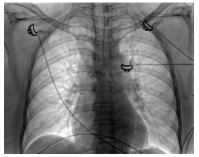

A 50-year-old female patient was evaluated at our center in February 2016 with history of hearing loss, inflammatory arthritis, and saddle nose for four years and new-onset worsening of hoarseness of voice, cough and breathlessness for three months. She was being treated as GPA based on clinical features and anti-myeloperoxidase (MPO) positivity with oral steroids and weekly methotrexate of 22.5 mg. Further evaluation showed normal complete blood count but raised erythrocyte sedimentation rate with normal urine examination, renal functions and liver functions. Chest X-ray did not show any infiltrates. Cardiac evaluation was normal. High-resolution computed tomography (HRCT) of the chest with neck cuts showed circumferential thickening of trachea (Figure 1).